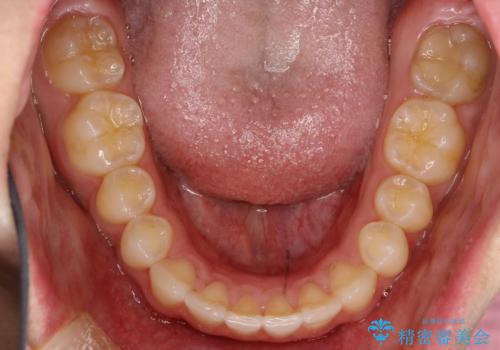

前歯の隙間がきになる インビザラインですきっ歯の治療

- 上の前歯の隙間を主訴に来院されました。

正中に隙間があり、かみ合わせが深い過蓋咬合という状態でした。

インビザラインにて矯正治療を行いました。